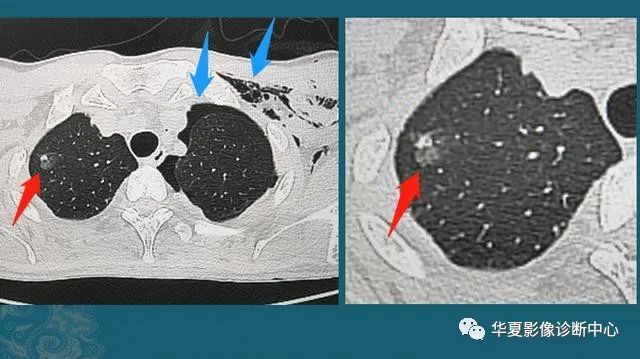

外伤后形成的小结节下图是一位30岁年轻人,车祸外伤,撞断3根肋骨,并造成肺挫伤、出血(创伤性湿肺):

红箭头这里的一小片肺组织被车祸撞击暴力撕裂,小血管破裂出血,形成不均匀的高密度影;蓝箭头是气胸和皮下气肿(肺破了,肺里空气溢出到胸腔和肌肉间隙内)。这种程度的创伤没有生命危险,保守治疗1周出院了,后来小伙子复查CT,肺里留下了一个3 mm的光滑小结节:

图2

这是个良性实性小结节,是血肿吸收不彻底形成的,不要紧,不需要定期复查。